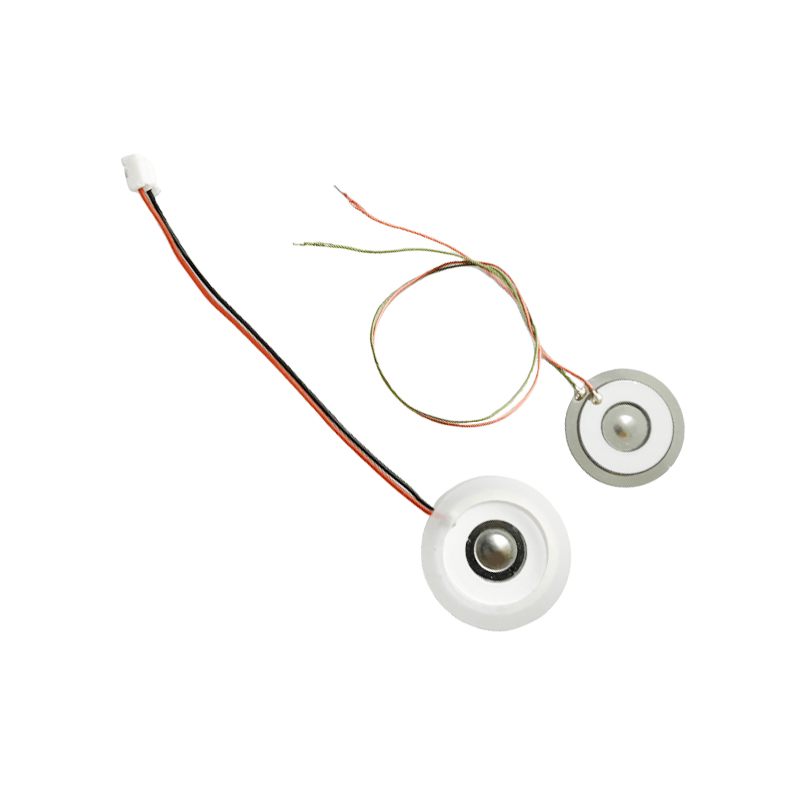

Polyimide (Polyimide) PI হিসাবে উল্লেখ করা হয়, জৈব পলিমার উপকরণের সর্বোত্তম ব্যাপক কর্মক্ষমতা, এটির চমৎকার রাসায়নিক স্থিতিশীলতা রয়েছে এবং পরমাণুযুক্ত ট্যাবলেটগুলির কার্যকারিতা দীর্ঘমেয়াদী ব্যবহার নিশ্চিত করতে বিভিন্ন ধরণের ওষুধের ক্ষয় সহ্য করতে পারে। উপরন্তু, পলিমার PI ফিল্মের তাপীয় স্থিতিশীলতাও চমৎকার, তাপমাত্রা পরিসীমা -200 ~ 300 ° C, উচ্চ নিরোধক, পরিবেশগত সুরক্ষা এবং অ-বিষাক্ততার দীর্ঘমেয়াদী ব্যবহার সহ, একটি বিশেষ প্রকৌশল উপাদান হিসাবে, মহাকাশ মাইক্রোইলেক্ট্রনিক্স ন্যানো-তরল ক্রিস্টাল বিভাজন ক্ষেত্রের মেম্বার অন্যান্য শতাব্দীর অন্যতম এবং অন্যান্য দেশের অন্তর্ভুক্ত ছিল। সবচেয়ে প্রতিশ্রুতিশীল প্রকৌশল উপকরণ, এবং এটি সহজ নয় উচ্চ-তাপমাত্রা নির্বীজন প্রক্রিয়ার মধ্যে বিকৃত করা, পণ্য পুনরায় ব্যবহার করা হয় তা নিশ্চিত করতে! যৌনতা এবং নিরাপত্তার জন্য, আমরা লেজারের ছিদ্রের জন্য লেজার প্রযুক্তি ব্যবহার করি, স্টেইনলেস স্টীল এবং পাইজোইলেকট্রিক শীটের মধ্যে ইমপ্লান্ট করা PI ফিল্ম, পাইজোইলেকট্রিক সিরামিক অতিস্বনক প্রযুক্তির ব্যবহার যাতে PI ফিল্মের মাধ্যমে পরমাণুযুক্ত ফোঁটাগুলি 3 ~ 4 μm কণার পরমাণুকরণে বিচ্ছুরিত হয়, মেডিক্যাল নেবুলাইজেশনের ব্যবহারকারীদের নিরাপত্তার জন্য মেজর নেবুলাইজেশন, মেডিক্যাল নেবুলাইজেশন তৈরি করে। PI এর সাথে নন-ক্লগিংয়ের প্রধান সুবিধা, গর্তের ভেতরের প্রাচীরটি মসৃণ এবং বৃত্তাকার, তরলের কোন অবশিষ্টাংশ নেই, সূক্ষ্ম এবং স্থিতিশীল এর পরমাণুকরণ। পরমাণুকরণ সূক্ষ্ম এবং স্থিতিশীল। পিআই ফিল্ম নেবুলাইজার ট্যাবলেট এটি কার্যকরভাবে ওষুধের অবশিষ্টাংশ প্রতিরোধ করতে পারে, ক্রস-দূষণের ঝুঁকি কমাতে পারে। ব্যবহারিক প্রয়োগে, পলিমার PI মেমব্রেন নেবুলাইজার ট্যাবলেটগুলির কম শক্তি খরচের বৈশিষ্ট্যগুলিও প্রতিফলিত হয়েছে, সংক্ষেপে, পলিমার PI মেমব্রেন নেবুলাইজার ট্যাবলেটগুলি এর চমৎকার কার্যকারিতা এবং ডিজাইনের সুবিধা সহ, মেডিকেল নেবুলাইজেশন থেরাপির ক্ষেত্রে একটি অপরিহার্য অংশ হয়ে উঠেছে৷